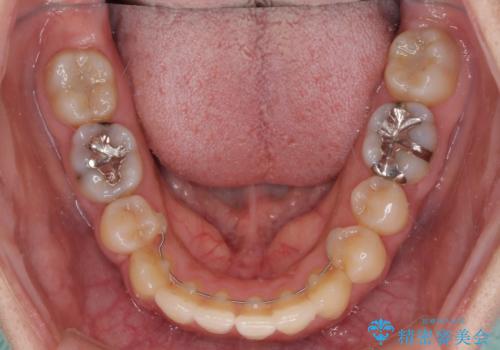

- 上下の八重歯を気にして来院された患者様です。

八重歯の後ろの歯を1歯抜歯し、補助装置(リンガルアーチ)を用いて八重歯の位置を改善し、その後インビザラインにより矯正治療を行うこととしました。

右側のみ上下小臼歯を抜歯したため、上下の正中が右にずれてしまう可能性があります。

また、元々右側は上下が咬み合っていないため、矯正をしても咬み合わないことも考えられました。

治療期間はかかりましたが、正中も合い、綺麗な仕上がりとなりました。